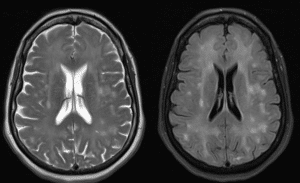

After ruling out infections and substance abuse, a head CT scan revealed no acute findings. Subsequently, an MRI of the brain with contrast was ordered to assess any structural abnormalities. The MRI revealed extensive FLAIR and T2 signal abnormality throughout the white matter of the bilateral cerebral hemisphere. Areas of restricted diffusion within the bilateral cerebral hemisphere were noted, indicative of hypoxic-ischemic injury supporting the diagnosis of DPHL. The pertinent images are shown below in Figure 1.

Figure 1: MRI of Brain without contrast (Left) & T2 FLAIR MRI of Brain without contrast (Right)

Both show extensive signal abnormalities throughout the white matter of bilateral cerebral hemispheres, suggestive of hypoxic-ischaemic injury.